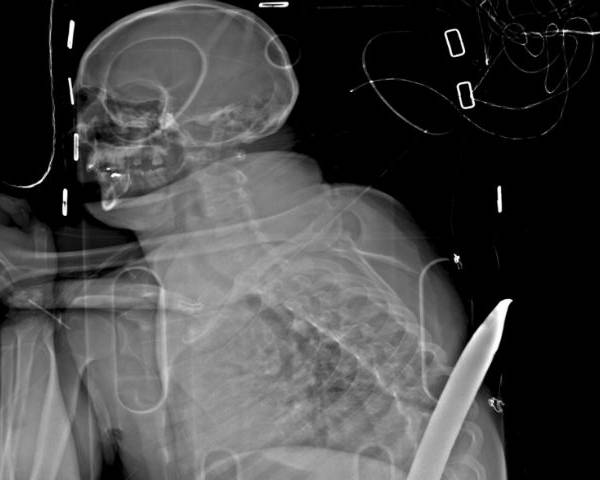

Hace tres años, un sudafricano sufrió un accidente minero que casi lo mata: una varilla industrial lo penetró de un lado al otro del cuerpo, entrando entre sus piernas y saliendo por su espalda, justo debajo de su omóplato. Ahora Daniel de Wet se clasificó para correr el próximo domingo en el ultramaratón Comrades.

De Wet perdió uno de sus riñones y sufrió otras lesiones internas por la palanca metálica de 1,8 metros (5,9 pies).

El terrible accidente ocurrió en enero de 2015, cuando cayó en la varilla en una mina en Carletonville, una zona minera de oro cerca de Johannesburgo. Con la palanca aún clavada, estuvo consciente mientras lo subieron a la superficie en una camilla. Los rescatistas lo transportaron en avión a un hospital, donde los cirujanos retiraron la palanca. De Wet fue dado de alta 19 días después.